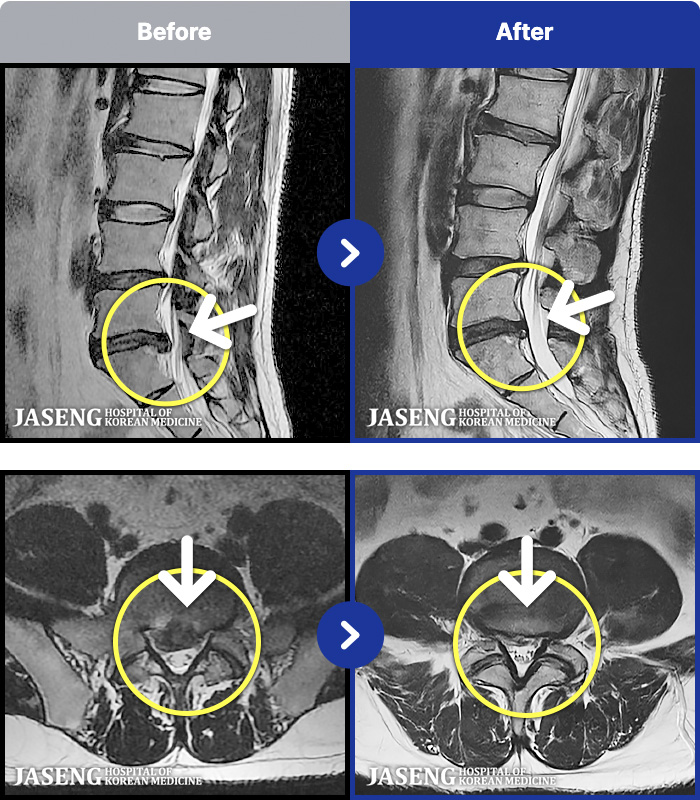

[Կñ:22.12.23~24.12.04]

[_㸮ũ] 㸮

No.45

ȸ 576

2024.12.24